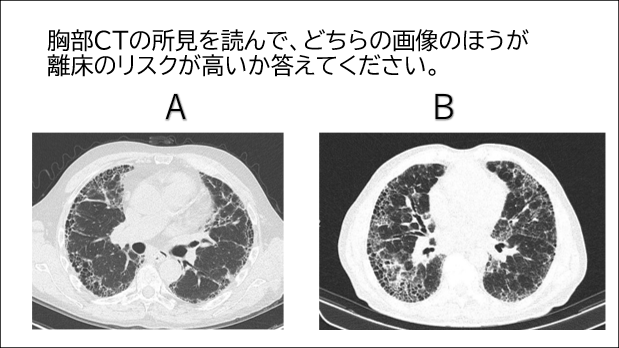

今回は新講座「即戦力の「知」が身につく疾患別BESTアプローチ 間質性肺炎編」の内容から、画像に関する問題をシェアします。2つの画像のうち離床のリスクが高いのはどちらでしょうか?

[画像問題の解答例]

Bの方がリスク管理が高いと考えられる。両方とも胸膜化に蜂巣肺が広がり、牽引性気管支拡張症を認めますが、Bの方がその範囲が広範囲であるため。

※上記、間質性肺炎のアプローチ講座で詳しく解説します。

画像提供:radiopaedia.org